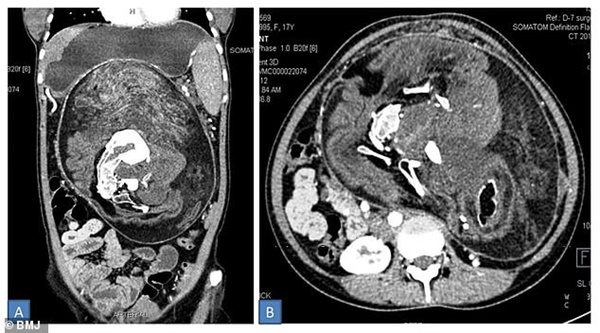

Các bác sĩ quyết định chụp cắt lớp để xem xét khối u một cách rõ ràng và họ phát hiện ra bên trong nó có chứa các bộ phận và mô. Một số chỗ trông giống như mỡ, những khu vực khác xuất hiện như các mô mềm của các cơ quan trong cơ thể. Khi kiểm tra kỹ hơn, lượng canxi tồn tại không chỉ là các chất cặn lắng đọng, chúng trông giống như xương - cụ thể là đốt sống, xương sườn và "xương dài".

Ảnh chụp CT cắt lớp của khối u kì lạ trong bụng cô gái 17 tuổi, có thể nhìn thấy phần xương màu trắng.

Khối u của cô có khả năng là một cặp sinh đôi dị dạng cùng phát triển trong bụng mẹ, bị hấp thụ vào cơ thể của cô gái và không thể phát triển thêm nữa. Các bác sĩ lý giải, trong bụng người mẹ khi ấy mang 3 thai nhi. Một trong ba thai phát triển và lấn lướt 2 thai kia, khiến chúng không phát triển bình thường.